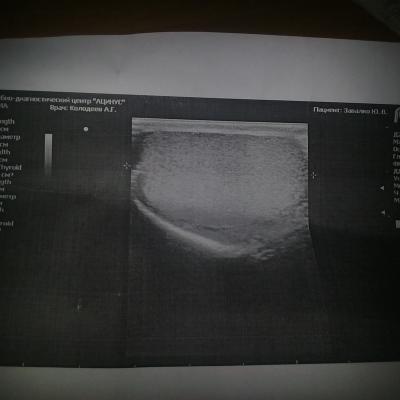

Нечитаемый текст.